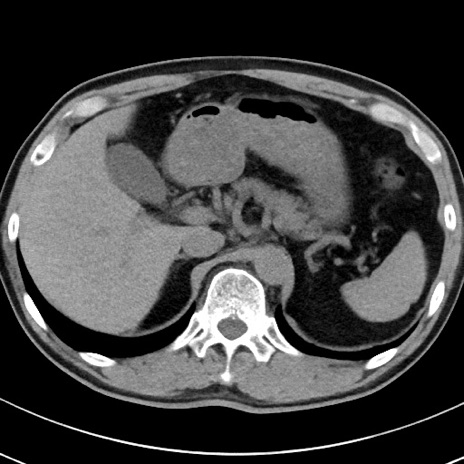

【腹部TIPS】症例29 参考症例 CT(横断像)

症例

70歳代男性